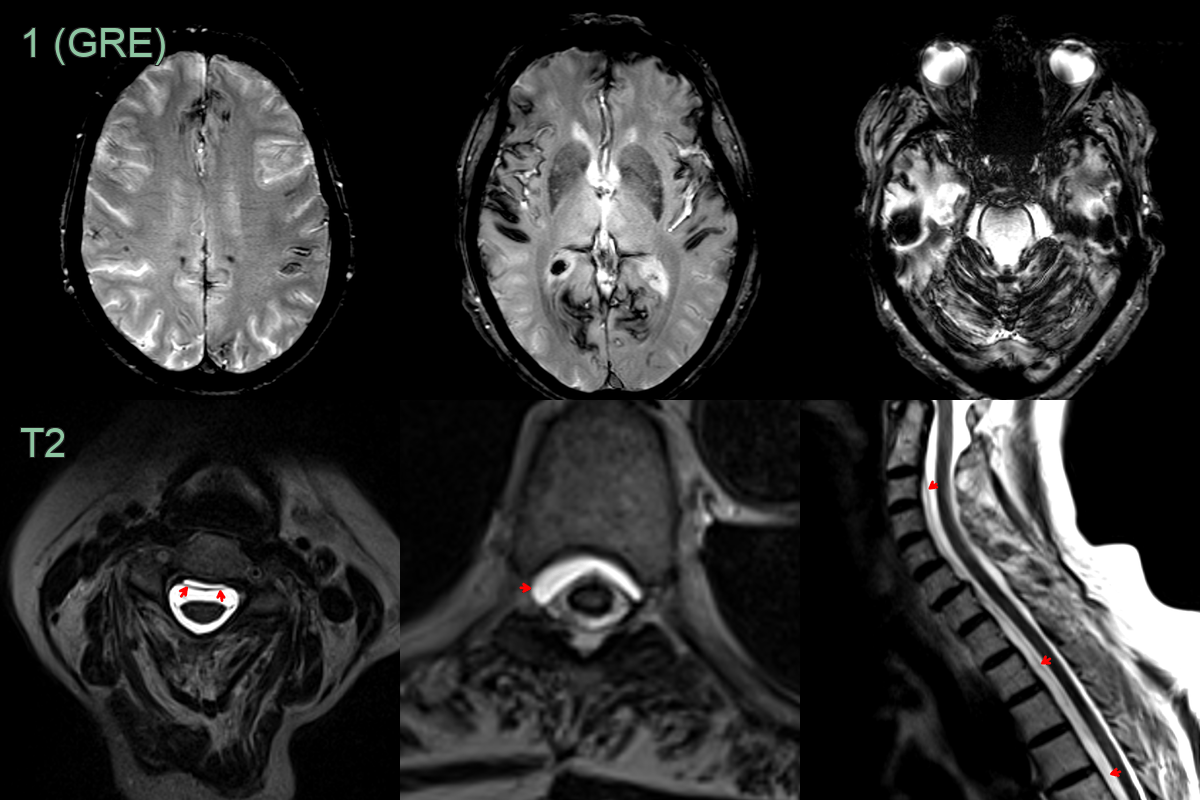

- A 70-year-old patient presented with tinnitus and dizziness.

- MRI showed extensive superficial siderosis above and below the tentorium.

- While the patient had no headache, given the distribution of siderosis, a CSF leak was suspected.

- MRI of the spine showed a longitudinally extensive ventral epidural collection, indicating a CSF leak.